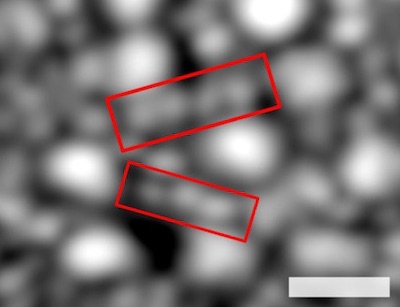

Trials on two human patients were carried out, using the platform to measure the deformations of rods and cones in response to stimulus light flashes of varying intensity and generating all-optical recordings of light-induced activity in the retina, or optoretinograms.

Cones and rods were automatically identified in the registered images and axially segmented in the OCT volumes, providing 3D tracking of photoreceptors over time. The responses of the cells could be seen to increase as the light intensity increased until saturation occurred.